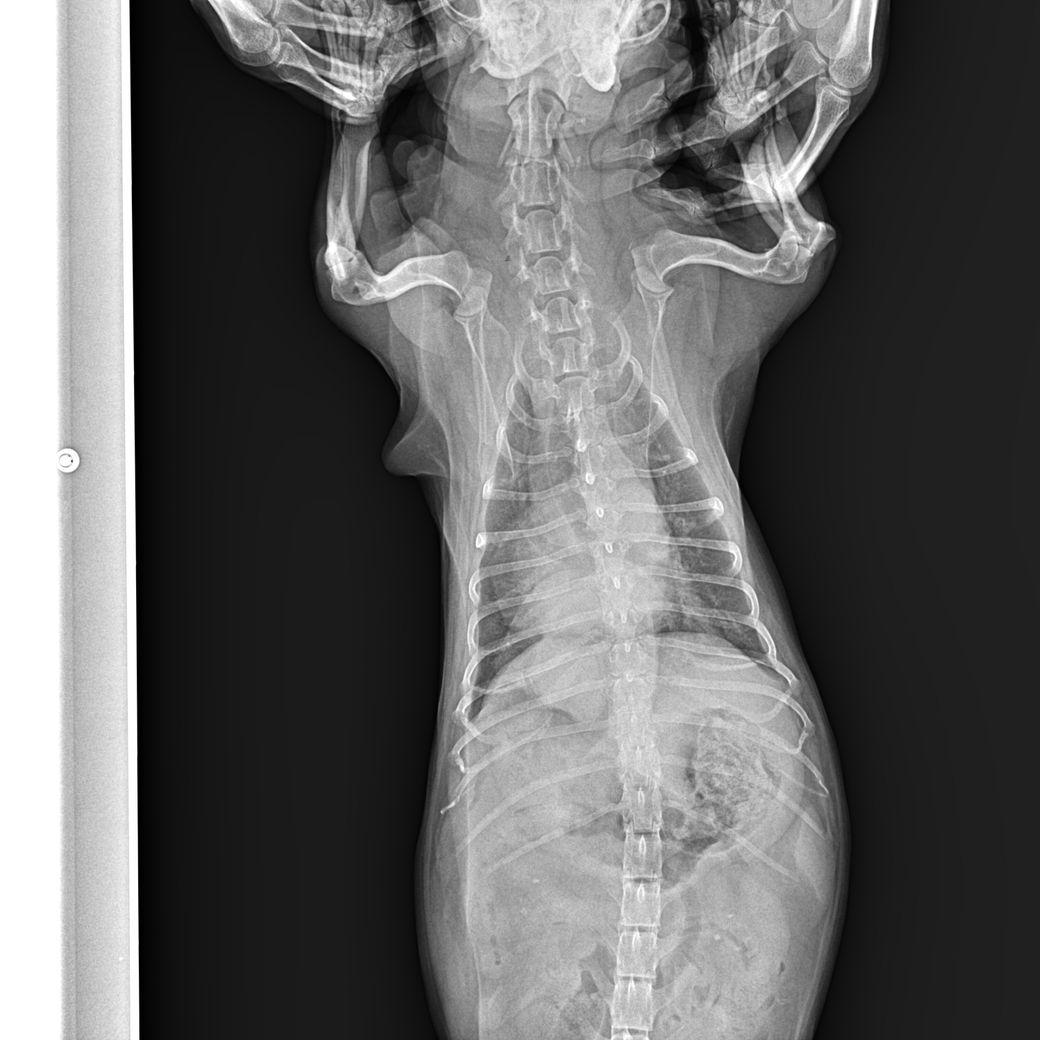

강아지가 식욕 저하와 기침을 많이 하고 거품 토를 해서 진료를 봤습니다. 헥헥거리는 증상도 있었습니다.

약을 처방받고 기침은 많이 줄었는데 방사선상으로 폐부분이 하얗게 보입니다.

2. 폐가 하얗게 보이는데 가능성은 높은 질병은 무엇일까요? CT가 정확하겠지만 상황이 되지 않아 문의드립니다.

또한 폐쪽도 강아지가 긴장하고 통증을 호소하게 되는 경우 호흡이 빠르므로 호기시 촬영한다면 폐가 뿌옇게 보일 수도 있습니다.

폐 후엽 의 내측면에 종괴성 병변이 관찰되며 원발성 폐종양의 호발 부위로

1. 이부분의 압박으로 식도가 눌리기 때문에 음식물을 먹을때 통증을 호소할 수 있고

2. CT를 찍어 확인할 필요가 있으나, 원발성폐종양, 식도종양, 폐농양, 식도게실, 육아종성병변 등을 고려해야합니다. 이는 CT로 어느정도 감별가능합니다

폐종양의 특징은 말기직전까지 "기침은 거의 하지 않습니다. 호흡도 괜찮습니다."라는 보호자의 병력이 특징적입니다. CT촬영 하시기 바랍니다.